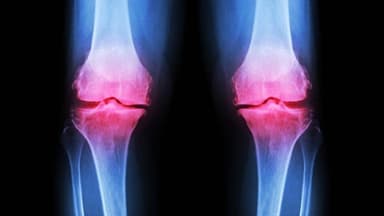

Khi thoái hóa khớp gối tiến triển đến giai đoạn 3, người bệnh sẽ càng cảm nhận rõ hơn các cơn đau tại khớp gối. Lúc này, lớp sụn khớp bao bọc quanh đầu xương đã có dấu hiệu bào mòn đáng kể. Mô mềm quanh khớp cũng bị viêm dẫn đến tình trạng viêm bao hoạt dịch. Hình ảnh trên phim chụp X-quang còn thấy rõ các gai xương phát triển nhiều hơn, khe khớp giữa các đầu xương bị thu hẹp thấy rõ.

So với các giai đoạn trên, thoái hóa khớp gối ở giai đoạn 4 đã có những biểu hiện nghiêm trọng hơn hẳn. Lớp sụn khớp gần như bị bào mòn và bong tróc hoàn toàn để lộ đầu xương rõ rệt. Gai xương hình thành nhiều và có kích thước ngày càng lớn, khoảng cách giữa hai đầu xương cũng bị thu hẹp đáng kể. Lượng dịch bôi trơn khớp giảm đi còn khiến các đầu xương dễ dàng cọ xát với nhau gây ra những cơn đau nhức nghiêm trọng.